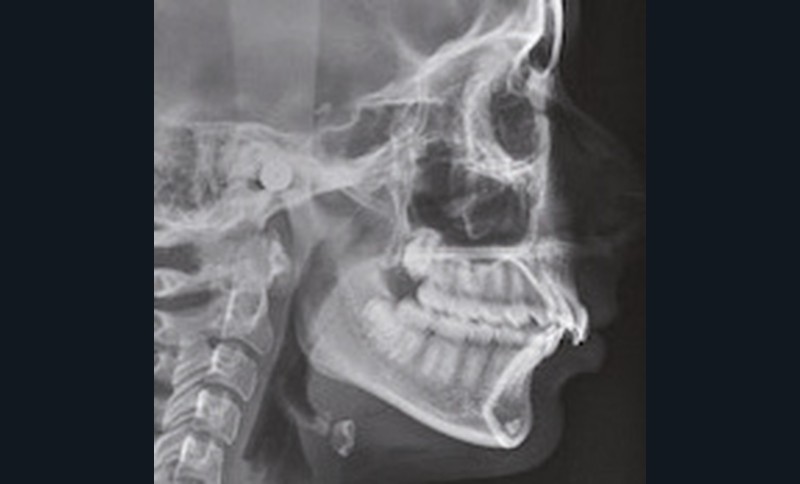

Examen clinique (fig. 1 à 7)

Son visage de face est équilibré et symétrique ; en revanche, au niveau de son profil elle présente une rétromandibulie avec un sillon labio-mentonnier marqué.

À la vue de l’examen radiographique, elle est au stade CS6 d’après la méthode de maturation vertébrale de Baccetti [1]. Elle présente une classe II squelettique de Ballard par rétrognathie mandibulaire avec un ANB de 9° et un AoBo de 9 mm sur un schéma facial normo-divergent. L’incisive mandibulaire est vestibulo-versée (IMPA = 114°). Le maxillaire est bien positionné. Elle présente de plus une dysharmonie dento-dentaire (DDD) antérieure par excès mandibulaire.